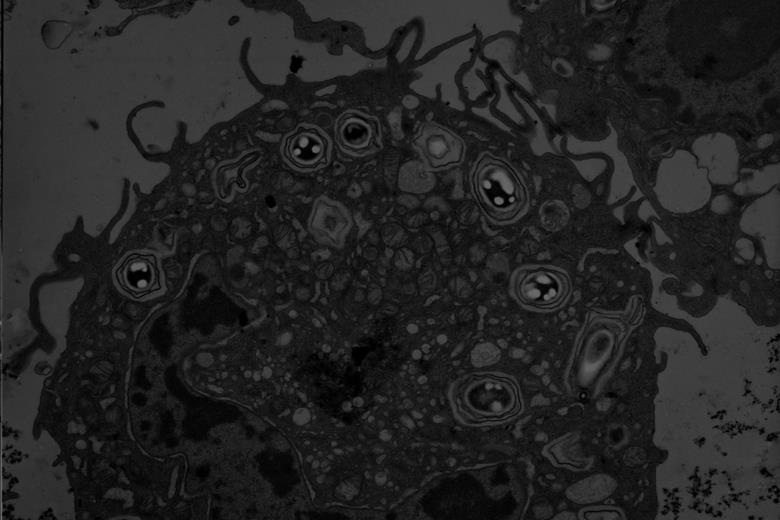

5293_thumbnail_basporesinamurinemacrophage_632955_crop (1).jpg